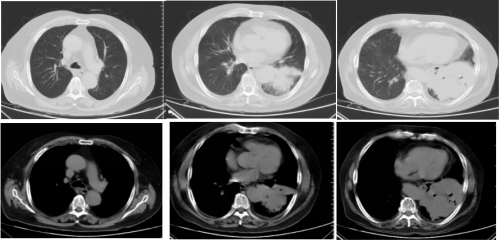

10月14日胸部CT检查:

10-20胸部CT: